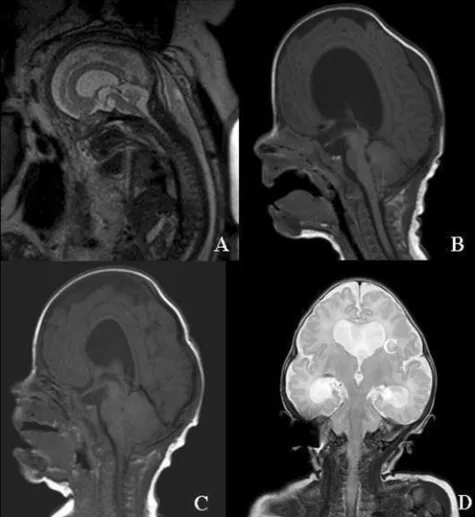

图5综合征性颅缝早闭中Chiari I畸形作为获得性、进行性病变——Crouzon综合征示例

a.胎儿MRI:后颅窝大小正常,小脑位置正常

b.生后1个月MRI:同一患儿后颅窝空间受限,小脑扁桃体开始下疝至枕骨大孔,伴活动性脑积水

c、d.3个月(2个月后)矢状T1(c)与冠状T2(d)MRI:Chiari I畸形及脑室扩张均进展,出现代偿性尖头畸形并颞窝膨出